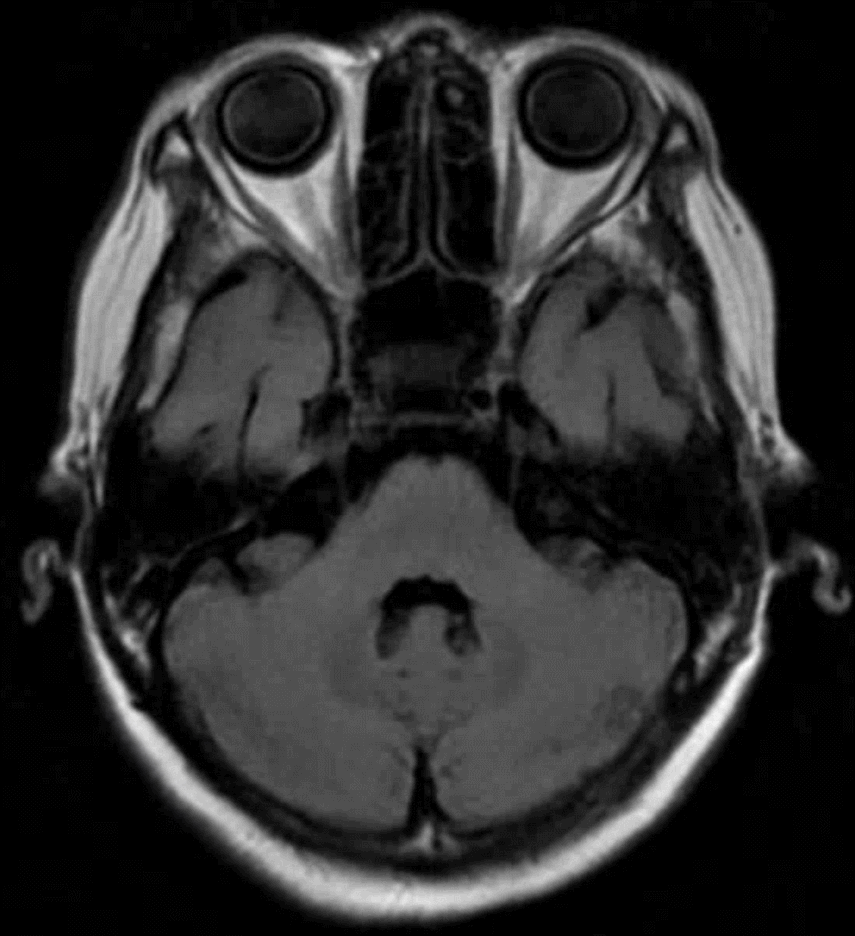

🔆  行头MRI+MRA示:脑内散在小缺血灶;老年性脑萎缩;双侧颈内动脉床突上段动脉瘤

MRI+MRA